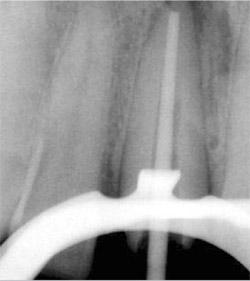

Root canal treatments using the crown-down technique and GuttaFlow filling material were performed on the canals of each case (Figure 5 and Figure 6). The crown structure of the teeth in Case One was restored with ParaPost Fiber White, and in Case Two with ParaPost Fiber Lux after post removal (Figure 7 and Figure 8). The posts were cemented with ParaCem, and the build-ups with ParaPost ParaCore, and full metal-ceramic crowns were posteriorly cemented as a part of the patients’ general treatment plan (Figure 9, Figure 10, Figure 11). Both cases were followed up on clinically for 12 months.

On the final periapical radiograph following obturation, the apical space, width, and length of the root canals were checked (Figure 5 and Figure 8). The working field was isolated with a rubber dam. Two thirds of the total canal length of the canals was used for the post space. The GuttaFlow was removed to the desired depth using a Touch’n Heat 5004 instrument (SybronEndo, Orange, CA) leaving 5 mm of GuttaFlow in the canals (Figure 8 and Figure 12).

A rotary reamer was selected according to the canal thickness on the radiograph using a template provided in the post system in both cases. The canals were prepared using a low-speed handpiece. For Case 1, a 4.5-mm rotary reamer was selected for the canals. ParaPost Fiber White drills was used with a slow-speed contra-angle. The 4.5 ParaPosts Fiber White were cut at the apical aspect to the required length with a diamond-finishing bur (Figure 7) in Case 1. A 5.5 ParaPost Fiber Lux was used in Case 2 (Figure 8).

| Figure 8 Radiograph of tooth No. 8 showing ParaPost Fiber Lux before cementation. | |||||||||